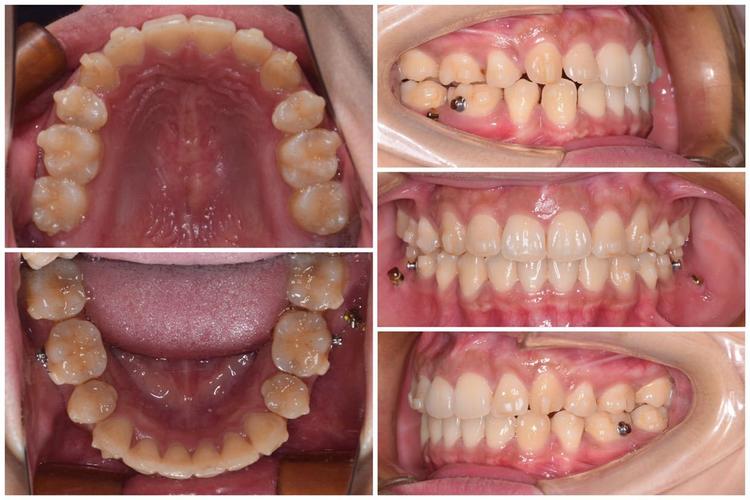

在技术特色上,梁甲兴医生以“精准、高效、舒适”为核心,构建了多元化的正畸技术体系,他擅长根据患者的牙齿畸形类型、骨骼发育情况、年龄及美观需求,灵活选择矫正方式,对于青少年患者,他注重早期干预,通过功能性矫治器、生长引导技术等,利用生长发育潜力纠正骨性畸形,避免成年后正颌手术;对于成人患者,他更兼顾功能与美学,结合隐形矫正(如隐适美、时代天使)、自锁托槽等技术,在缩短矫正周期的同时,减少对生活的影响,尤其对于骨性错颌畸形(如“地包天”“龅牙”)、牙齿严重拥挤、深覆合深覆盖等复杂病例,他通过数字化模拟设计(如口内扫描、3D打印模型)、微种植体支抗精准控制牙齿移动,实现了传统正畸难以达到的精细化效果。

在临床实践中,梁甲兴医生始终坚持以患者为中心的服务理念,他认为,正畸不仅是“排齐牙齿”,更是“重建咬合功能与面部美学”的过程,在方案设计阶段,他会通过详细的面部分析、口腔检查、X光片测量及数字化模拟,与患者充分沟通,明确矫正目标(如改善侧貌、调整微笑曲线等),确保方案既符合医学标准,又契合患者个人需求,一位23岁的女性患者因“龅牙”导致自卑,梁医生在全面评估后,采用隐形矫正结合微种植体支抗,内收前牙改善突度,同时通过垂直向控制优化下颌平面,最终不仅牙齿排列整齐,侧貌也变得柔和自然,患者术后反馈“终于能自信大笑”。

梁医生对矫正过程中的细节把控尤为严格,从托槽粘贴的精准度到弓丝更换的力度,从复诊时口腔卫生的指导到附件粘接的美学考量,他都亲力亲为,最大限度减少患者的不适感,对于矫正后的保持阶段,他强调长期维护的重要性,为患者定制个性化保持器,并定期跟踪回访,防止复发。